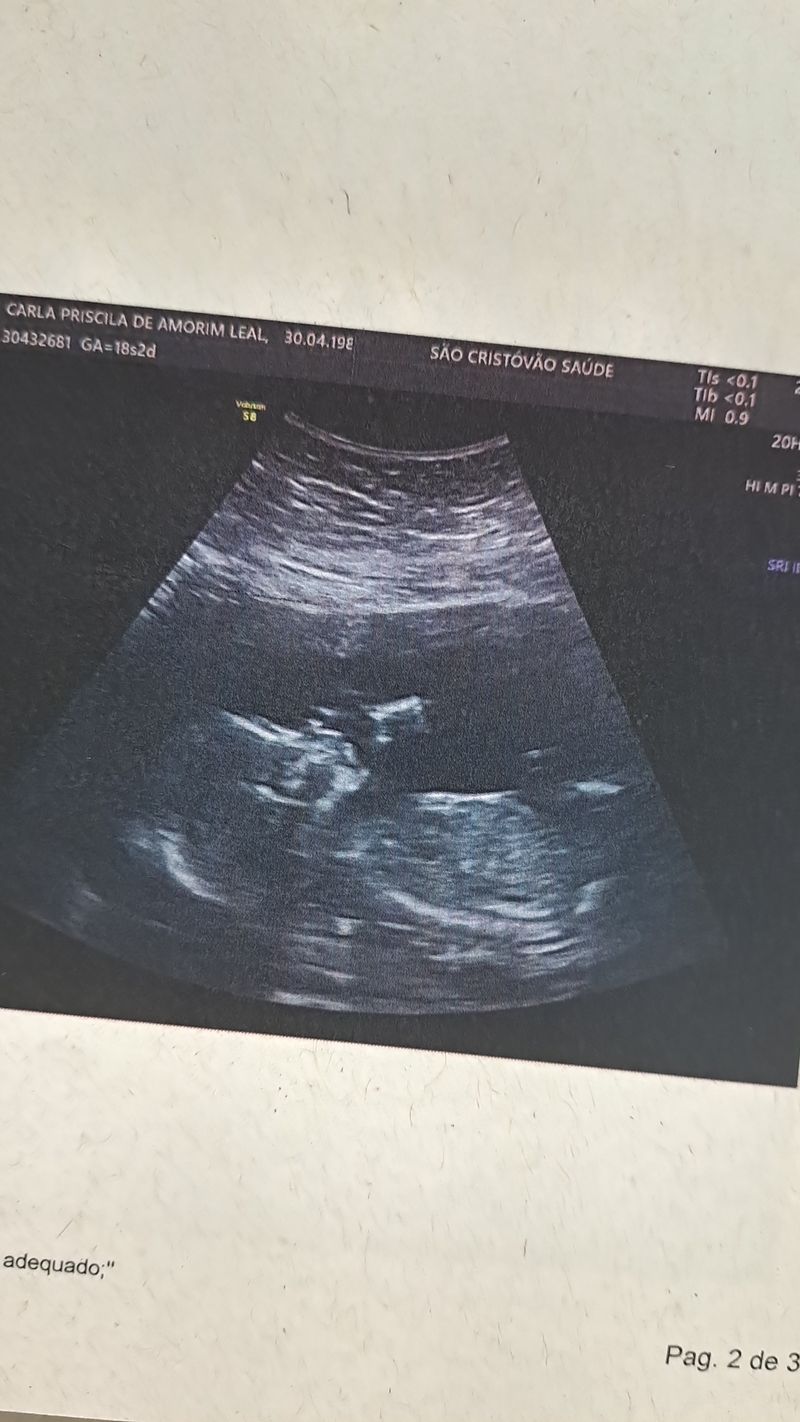

Minhas primeiras fotinhas

Eu ainda estou no forminho, mas a mamãe já tem várias fotos e vídeos, confere aí em baixo meu pessoal! 👶